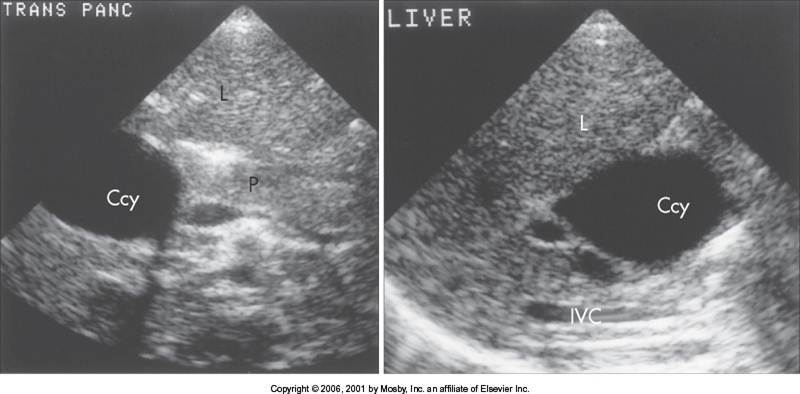

Cholelithiasis